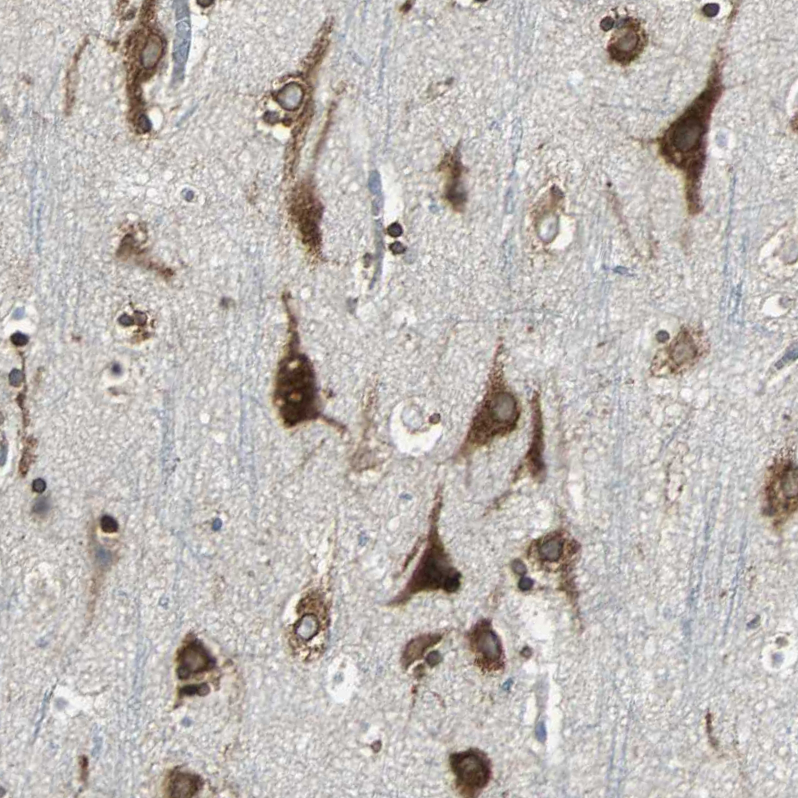

Immunohistochemical staining of human cerebral cortex, lymphoid tissues, pancreas and skeletal muscle using Anti-SYVN1 antibody HPA005480 (A) shows similar protein distribution across tissues to independent antibody HPA024300 (B).